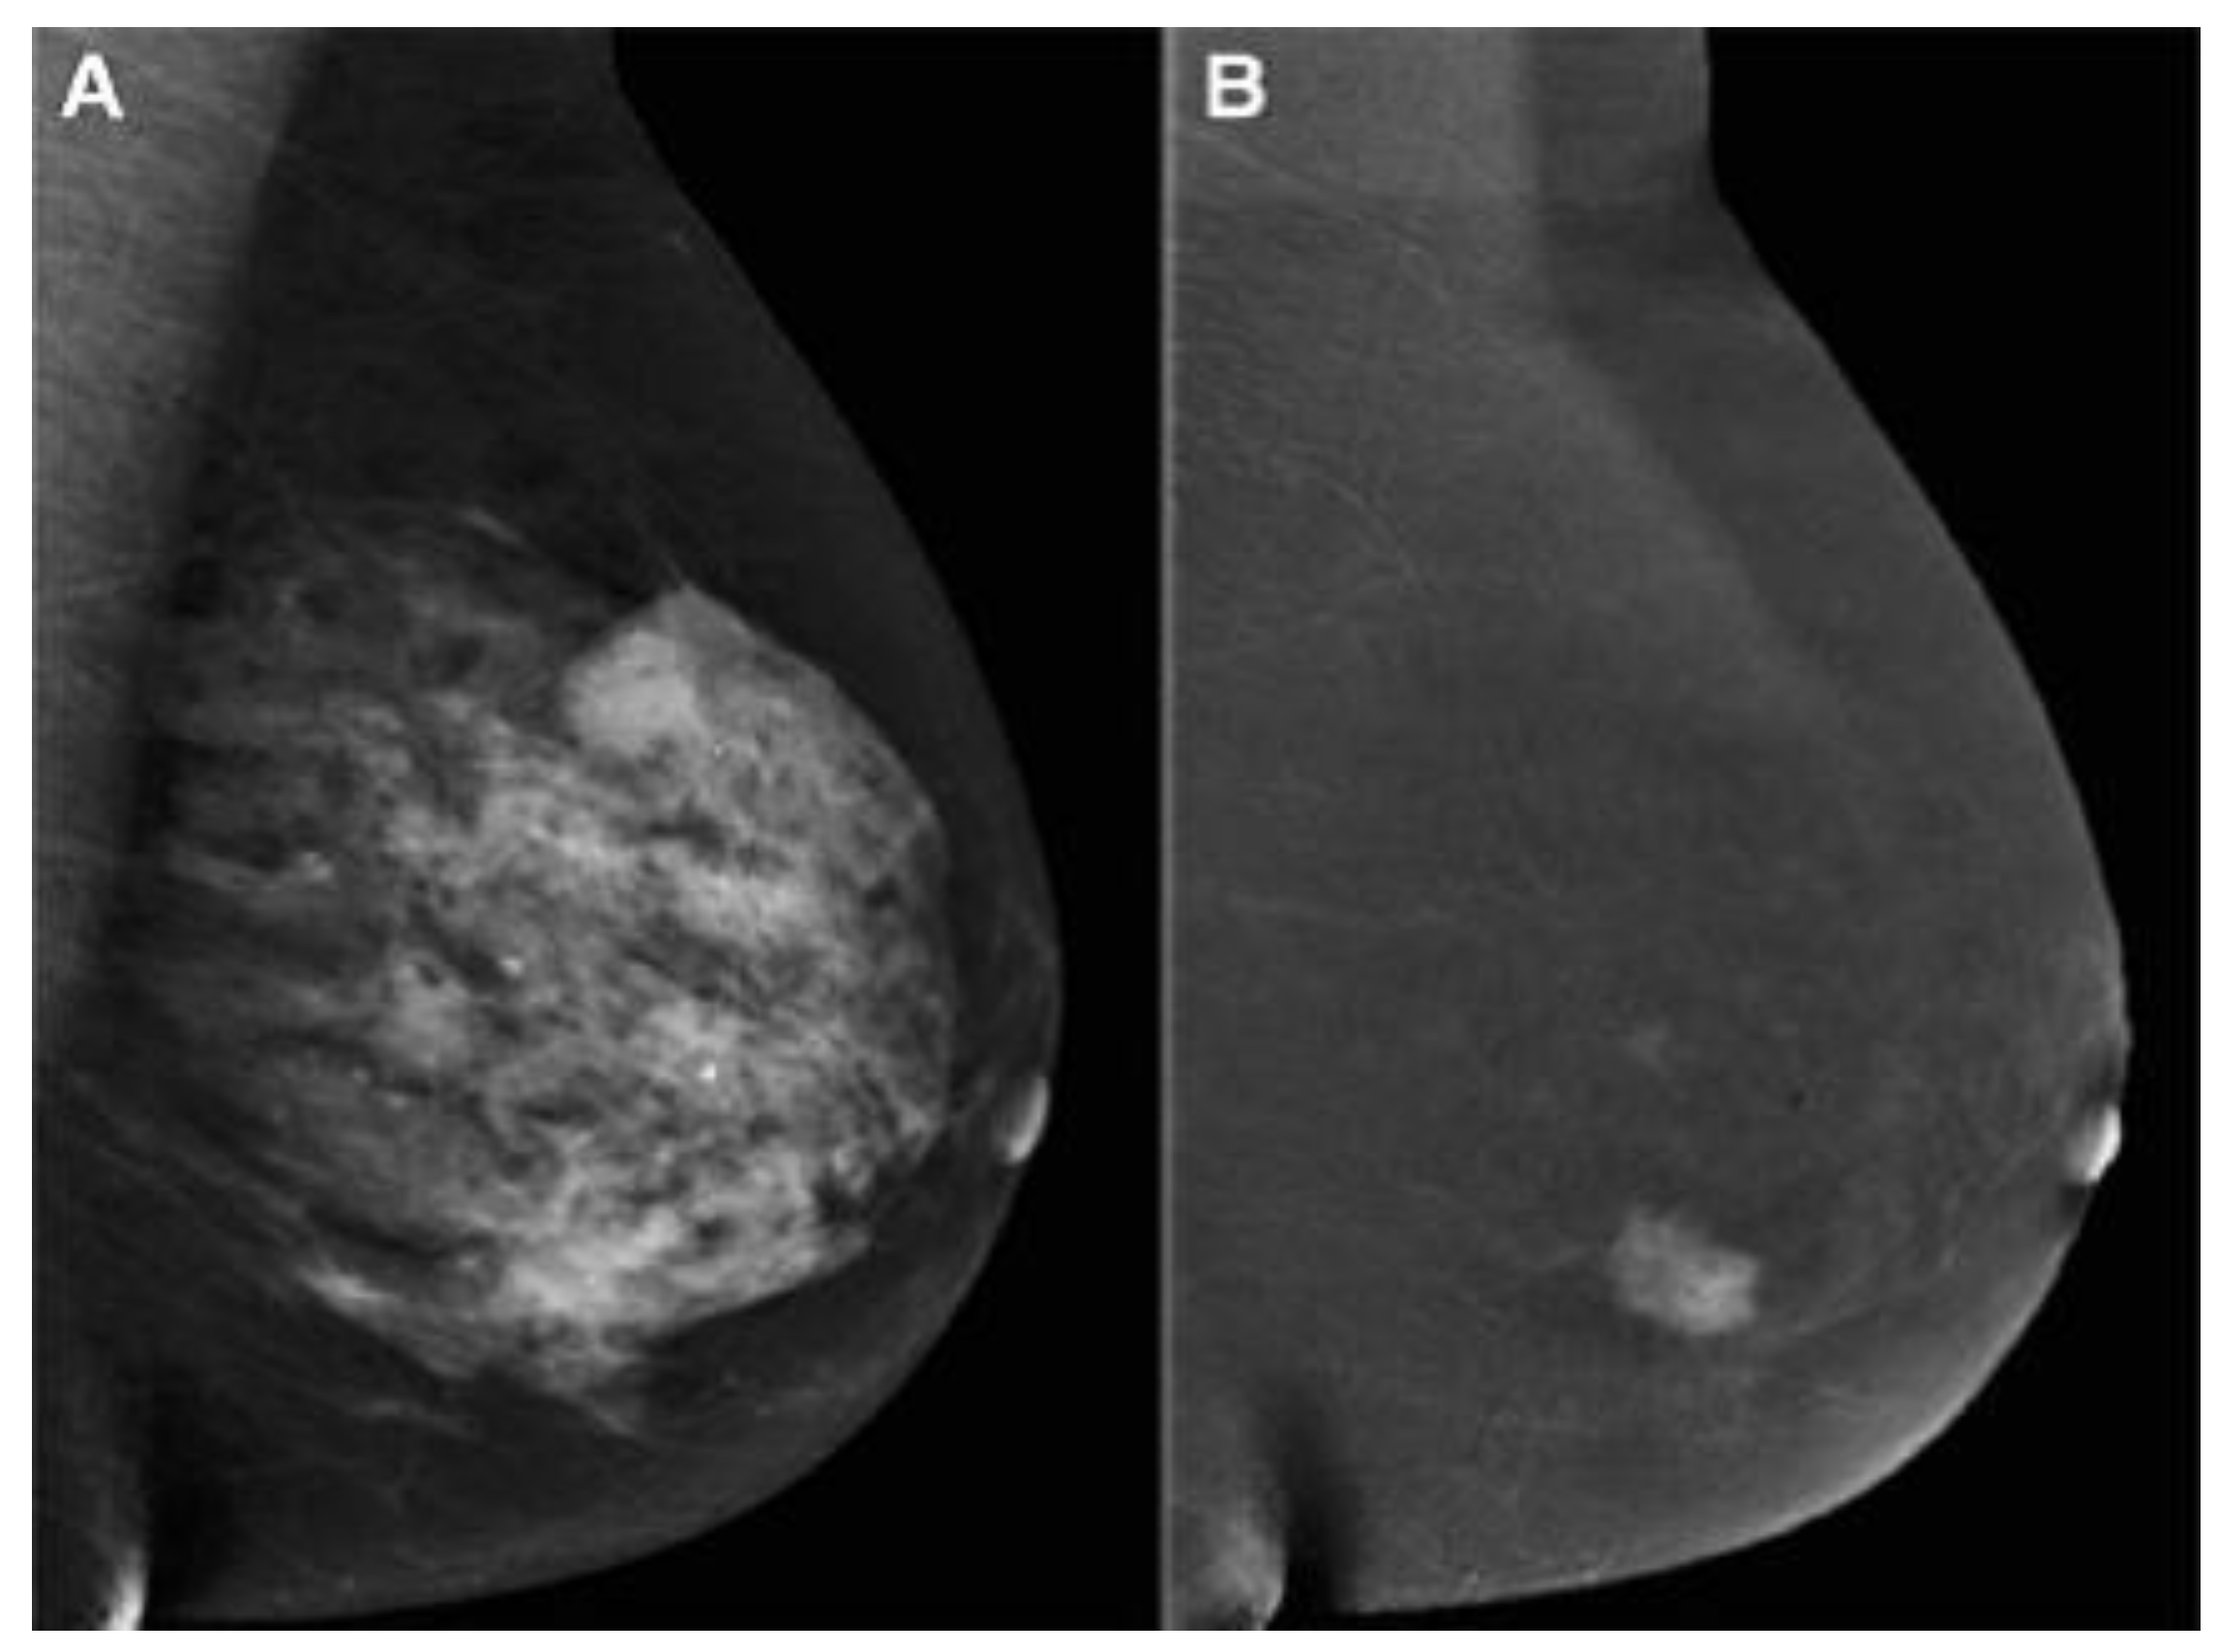

2.3. Contrast-enhanced mammography (CEM)

- Ghaderi, K.F.; Phillips, J.; Perry, H.; Lotfi, P.; Mehta, T.S. Contrast-enhanced mammography: current applications and future directions. Radiographics 2019, 39, 1907–1920. [Google Scholar] [CrossRef] [PubMed]

- Jochelson, M.S.; Dershaw, D.D.; Sung, J.S.; Heerdt, A.S.; Thornton, C.; Moskowitz, C.S.; Ferrara, J.; Morris, E.A. Bilateral contrast-enhanced dual-energy digital mammography: feasibility and comparison with conventional digital mammography and MR imaging in women with known breast carcinoma. Radiology 2013, 266, 743. [Google Scholar] [CrossRef]

- Mori, M.; Akashi-Tanaka, S.; Suzuki, S.; Daniels, M.I.; Watanabe, C.; Hirose, M.; Nakamura, S. Diagnostic accuracy of contrast-enhanced spectral mammography in comparison to conventional full-field digital mammography in a population of women with dense breasts. Breast Cancer 2017, 24, 104–110. [Google Scholar] [CrossRef] [PubMed]

- Sorin, V.; Yagil, Y.; Yosepovich, A.; Shalmon, A.; Gotlieb, M.; Neiman, O.H.; Sklair-Levy, M. Contrast-enhanced spectral mammography in women with intermediate breast cancer risk and dense breasts. AJR Am J Roentgenol 2018, 211, W267–W274. [Google Scholar] [CrossRef] [PubMed]

- Sudhir, R.; Sannapareddy, K.; Potlapalli, A.; Krishnamurthy, P.B.; Buddha, S.; Koppula, V. Diagnostic accuracy of contrast-enhanced digital mammography in breast cancer detection in comparison to tomosynthesis, synthetic 2D mammography and tomosynthesis combined with ultrasound in women with dense breast. The British Journal of Radiology 2021, 94, 20201046. [Google Scholar] [CrossRef]

- Li, L.; Roth, R.; Germaine, P.; Ren, S.; Lee, M.; Hunter, K.; Tinney, E.; Liao, L. Contrast-enhanced spectral mammography (CESM) versus breast magnetic resonance imaging (MRI): a retrospective comparison in 66 breast lesions. Diagnostic and interventional imaging 2017, 98, 113–123. [Google Scholar] [CrossRef]

- Bozzini, A.; Nicosia, L.; Pruneri, G.; Maisonneuve, P.; Meneghetti, L.; Renne, G.; Vingiani, A.; Cassano, E.; Mastropasqua, M.G. Clinical performance of contrast-enhanced spectral mammography in pre-surgical evaluation of breast malignant lesions in dense breasts: a single center study. Breast Cancer Research and Treatment 2020, 184, 723–731. [Google Scholar] [CrossRef]

- Chou, C.-P.; Lewin, J.M.; Chiang, C.-L.; Hung, B.-H.; Yang, T.-L.; Huang, J.-S.; Liao, J.-B.; Pan, H.-B. Clinical evaluation of contrast-enhanced digital mammography and contrast enhanced tomosynthesis—comparison to contrast-enhanced breast MRI. European journal of radiology 2015, 84, 2501–2508. [Google Scholar] [CrossRef]

- Huang, J.-S.; Pan, H.-B.; Yang, T.-L.; Hung, B.-H.; Chiang, C.-L.; Tsai, M.-Y.; Chou, C.-P. Kinetic patterns of benign and malignant breast lesions on contrast enhanced digital mammogram. PLOS ONE 2020, 15, e0239271. [Google Scholar] [CrossRef]